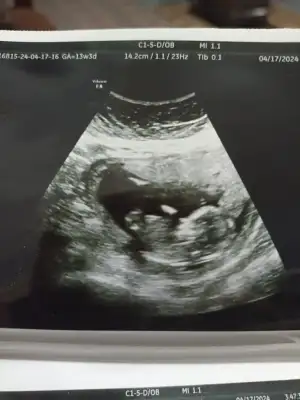

Merhabalar benimkini de yorumlayabilir misiniz acaba 🤗🤗 10+1 haftalık burda. Ama 6-7 gün fazla büyümüş yani 11+1 gibi 🤗🥰